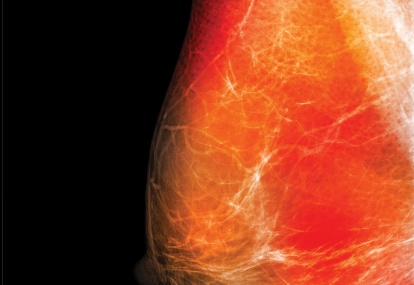

Oncology in focus: Breast cancer

Case study 1

A 40-year-old woman presented to the symptomatic breast clinic with a self-detected breast lump

Her medical history included obesity and depression. She was not on regular medications and had no allergies. She was working in a high level and stressful job, drank 10 units of alcohol a week...